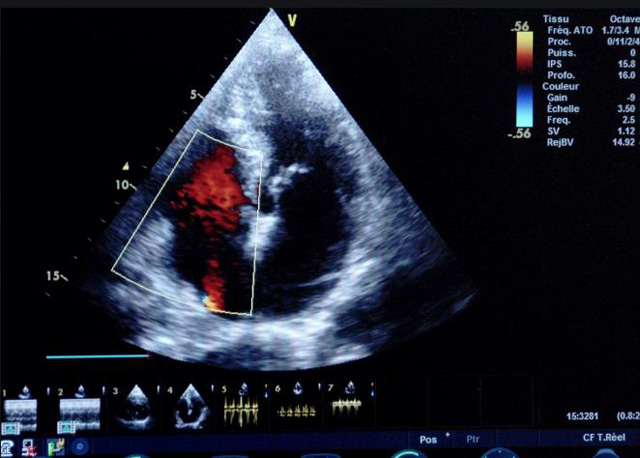

二、彩色室壁運動分析

(一)基本原理彩色室璧運動分析,從整體散射數據中識別心內膜邊界,並與前一幀彩色不同,心髒收縮或舒張期開始到結束時心內膜的全部過程。每一次順序顯示結束後,原來的彩色自動消失,以便進入下一個顯示過程。其結果是獲得對應於每一個心動周期的彩色顯示,描繪特定周期內室壁運動的時間運動軌跡。

(二)操作步驟根據背向散射數據中將心內膜運動的位移過程分類為組織或血液的原理,邊緣檢測跟蹤心內膜和血液的界麵。橙色表示收縮期的開始,收縮期不同時相逐幀顯示色彩均疊加在收縮末期最後一幀圖像中。檢查時,可按以下步驟進行:

①顯示較為理想的二維圖像,常用切麵有心尖四腔心、二腔心、左心室長軸和左心室乳頭肌水平短軸切麵。

③啟動CK係統,啟動後劃定感興趣區域。同時記錄的心動圖R波頂點為舒張末期,T波終點為收縮末期,顯示RT間期的CK彩階圖,連續記錄3~ 5個心動周期。

(三)檢測節段性室壁運動異常,研究冠心病患者左心室功能和分析局部室壁運動過程中。測量每一節段室壁的運動量,運動正常的節段彩帶色彩均勻層次光整。運動減弱的節段,厚度薄層次不全。心內膜位移幅度和速度均減低。心內膜位移幅度和速度甚低或難以測得。正常的多層彩帶消失,呈現紅色色帶,心內膜位移呈負向,幅度和速度亦減低。急性心肌梗死的患者中可用於識別存活心肌抑或壞死心肌。多巴酚丁胺負荷試驗存活心肌的心內膜位移幅度增高,停藥後即消失,而壞死心肌則無上述表現。實時檢查冠心病的節段性室壁運動異常,有時候通過發現局部心肌運動的時相異常,對於心髒傳導障礙的診斷也可能有幫助。